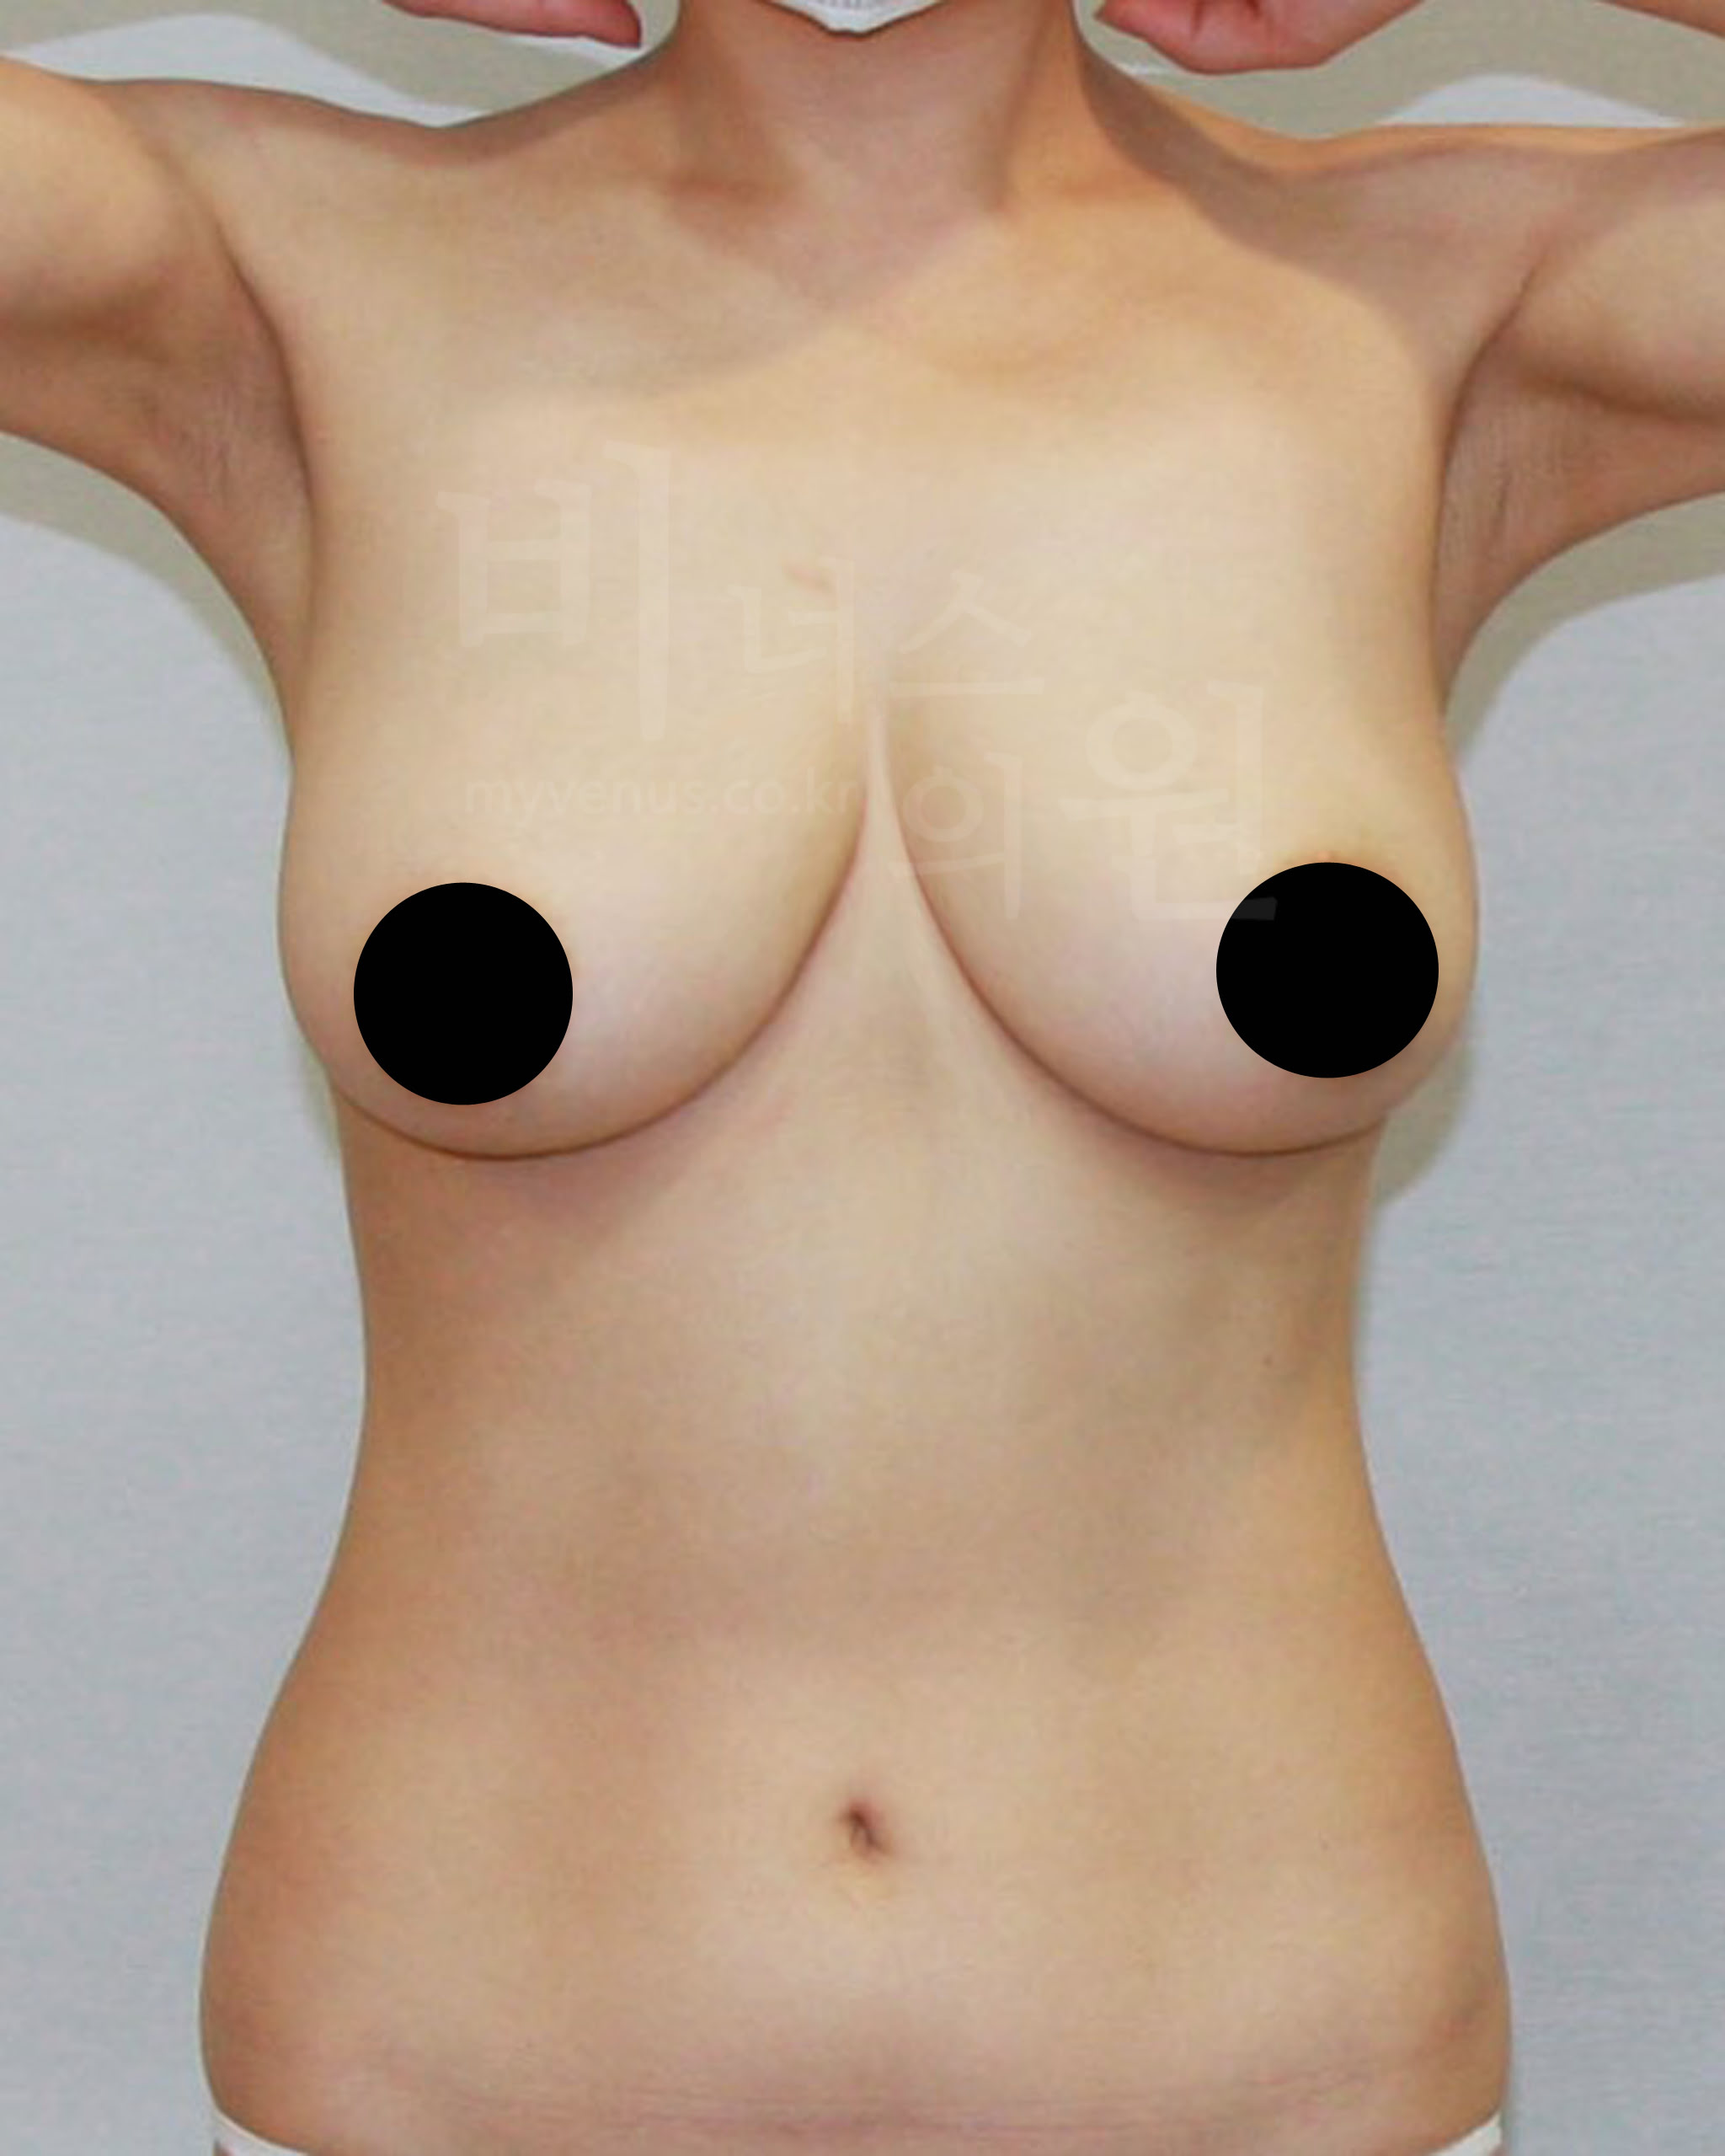

가슴축소 지방흡입 전, 한달 후 경과 사진으로 보는 효과

수술 부위 - 가슴 축소, 부유방, 겨드랑이, 유방 옆구리 지방흡입

가슴축소 지방흡입 전 사진

유방이 처지고 몸에 비해 큰 가슴 모습

가슴축소 지방흡입 후 사진

처짐 없이 사이즈가 감소와 리프팅 된 모습

젊은 여성분으로 무겁고 처진 가슴의 사이즈 감소를 위해 내원해 주셨어요. 가슴축소 지방흡입 후 가슴 사이즈가 주었으며, 처짐 없이 볼륨 업 된 가슴을 확인할 수 있어요. 가슴뿐만 아니라 부유방, 겨드랑이, 유방 옆구리 지방흡입을 함께 함으로써 주변 부위와 어색함 없어요.